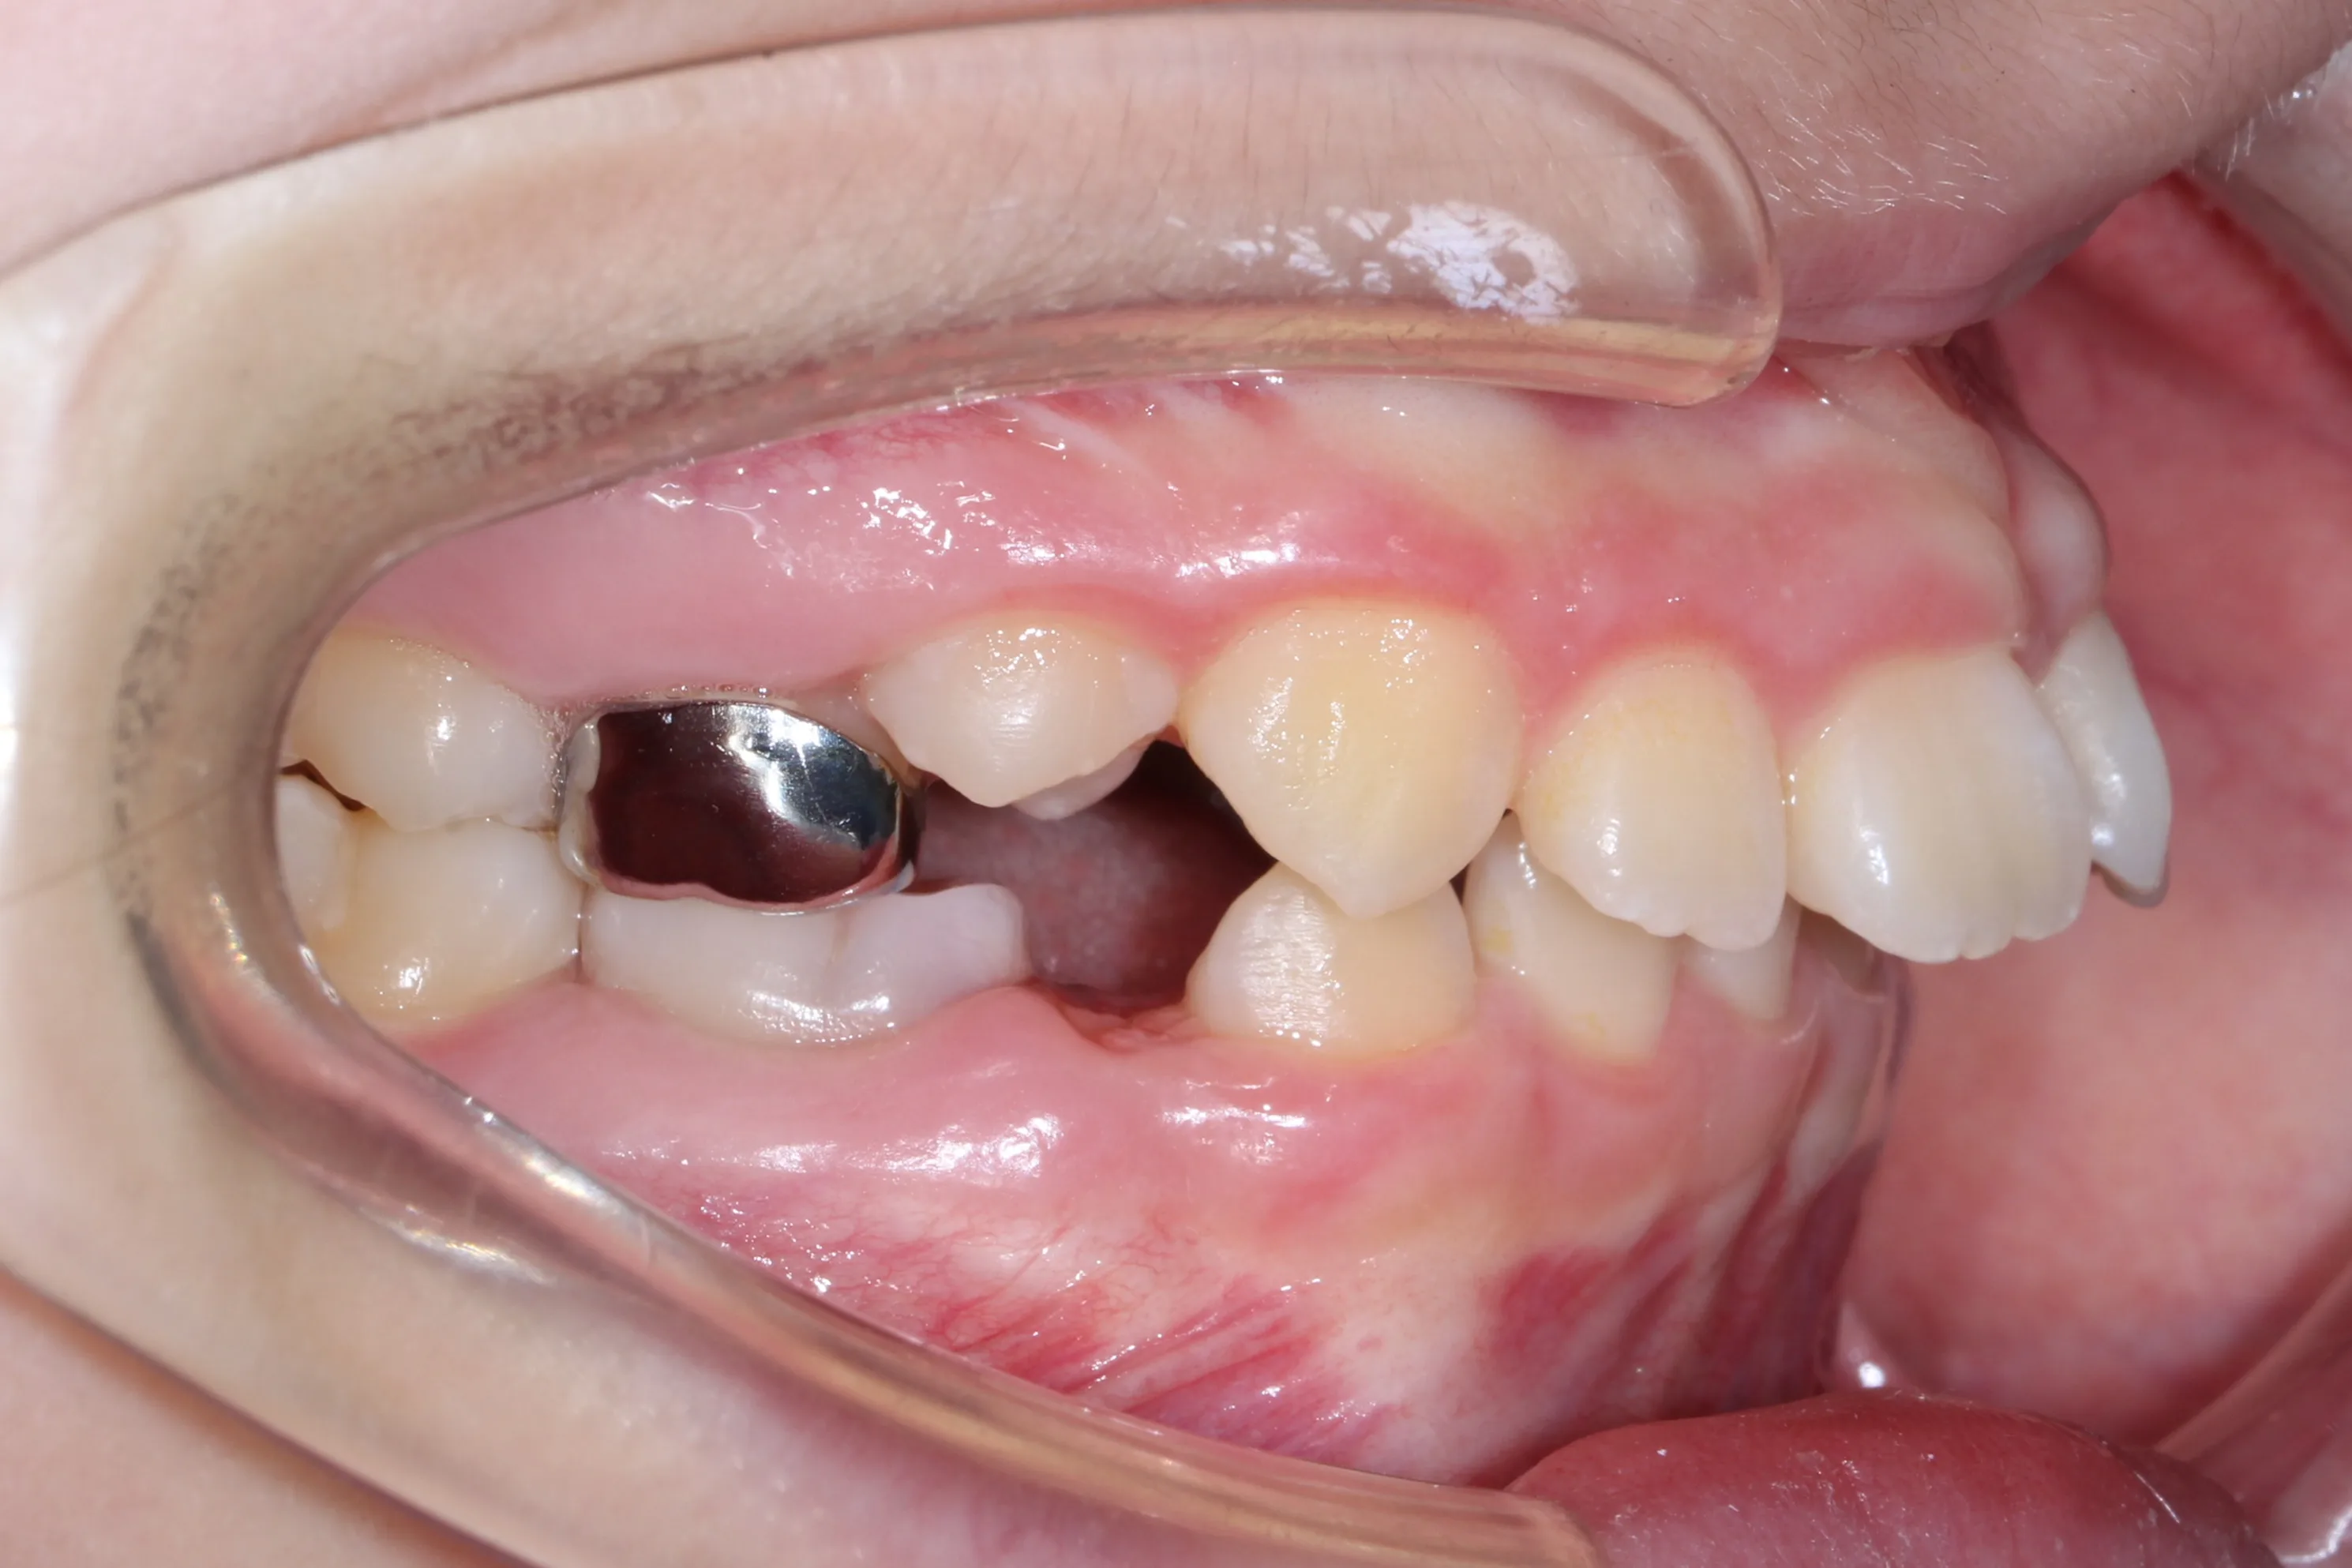

만 11세 환자분께서 튀어나온 앞니와 다물어지지 않는 입술 때문에 내원하셨습니다. 검진 결과 상악 전돌을 동반한 2급 부정교합(Class II malocclusion) 상태였으며, 아래턱의 성장이 다소 부족하여 골격적인 조화가 필요한 상황이었습니다.

이번 치료에는 인비절라인 퍼스트(Invisalign First)에 하악 전방 견인(Mandibular Advancement, MA wing)을 추가하여 치료를 진행하였습니다. 성장기라는 시기적 특성을 적극 활용하여 아래턱의 점진적인 성장을 유도하고, 과도한 상악 전치부 돌출을 개선하는 데 치료의 핵심 전략을 두었습니다.

2년 7개월의 치료 과정을 거치며 환자분의 협조도 덕분에 안모 프로파일과 교합이 안정적으로 개선되었습니다. 성장기라고 해서 무조건 교정이 어려운 것은 아닙니다. 적절한 시기에 맞춤형 장치를 선택한다면 골격적 불균형을 효과적으로 바로잡을 수 있습니다.